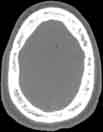

Visible Human male: Sectio transversalis 1035

CT

NMR

Pd T1 T2